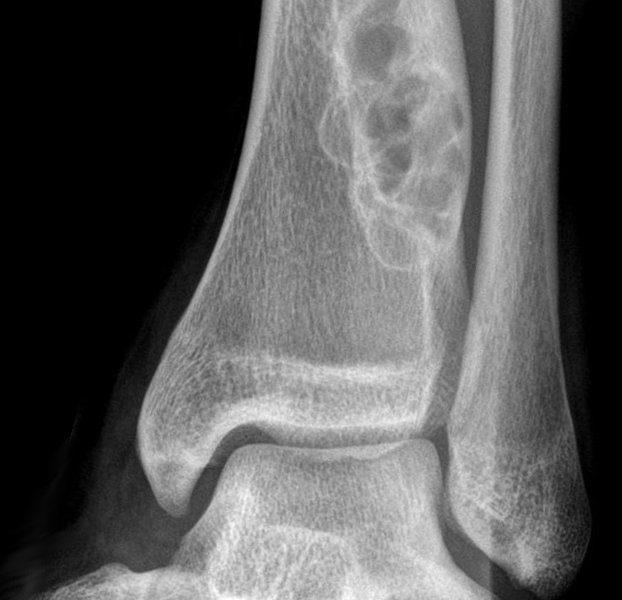

Market ScenarioFibrous dysplasia is a rare and chronic bone disorder in which fibrous tissue develops in place of normal bone, weakens the affected bone, and deform or fracture it. As per reports from The Johns Hopkins University, the exact cause of fibrous dysplasia is unknown, but it is believed to be due to a chemical irregularity in a specific bone protein. This bone protein abnormality may arise due to a gene mutation present at birth, although it is not known to be an inherited disorder.

It often results in uneven growth of bones, pain, brittle bones, and bone deformity. In fibrous dysplasia, the most commonly affected bones includes femur (thighbone), tibia (shin bone), ribs, skull, facial bones, humerus (the bone of the upper arm), pelvis, vertebrae in the spine (less often).

On the basis of diagnosis, it is segmented into X-rays, CT scans, MRI, bone scan, biopsy, and others.